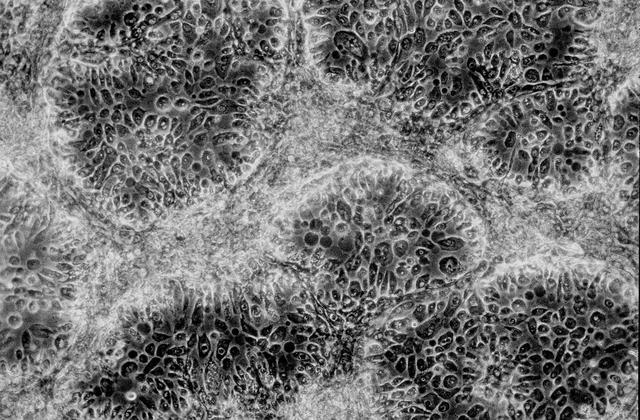

Isolation of human mammary epithelial cells (HMEC) from breast cancer susceptible tissue; A: Duct element recovered from breast tissue digest. B: Outgrowth of cells from duct element in upper right corner cultured in a standard dish; most cells spontaneousely die during early cell divisions, but a few will establish long-term growth. C: Isolate of long-term frowth HMEC from outgrowth of duct element; cells shown soon after isolation and in early full-cell contact growth in culture in a dish. D: same long-term growth HMEC, but after 3 weeks in late full-cell contact growth in a continuous culture in a dish. Note attempts to reform duct elements but this in two demensions in a dish rather than in three dimensions in tissue. NASA's Marshall Space Flight Center (MSFC) is sponsoring research with Bioreactors, rotating wall vessels designed to grow tissue samples in space, to understand how breast cancer works. This ground-based work studies the growth and assembly of human mammary epithelial cell (HMEC) from breast cancer susceptible tissue. Radiation can make the cells cancerous, thus allowing better comparisons of healthy vs. tunorous tissue. Credit: Dr. Robert Richmond, NASA/Marshall Space Flight Center (MSFC).